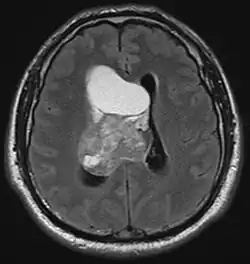

Nerwiak komórkowy ośrodkowy (ang. central neurocytoma) – rzadki, nowotworowy guz mózgu. Jest guzem o pośredniej złośliwości (II° według WHO). Został opisany w 1982 roku przez Hassouna i wsp[1]. Występuje równie często u kobiet i mężczyzn, zwykle około 30. roku życia. Objawia się klinicznie wodogłowiem, często niesymetrycznym. Uszkodzenie miąższu mózgu wywołuje później objawy ogniskowe. Leczeniem z wyboru jest resekcja guza, o ile zmiana zostanie usunięta całkowicie, rokowanie jest bardzo dobre.

Rozpoznanie opiera się na stwierdzeniu charakterystycznych cech histologicznych: polimorfizmu utkania guza, niewielkiej ilości mitoz, braku atypii, ekspresji markerów neuronalnych potwierdzonej badaniem immunohistochemicznym i (lub) stwierdzeniem wykładników zróżnicowania neuronalnego na poziomie ultrastrukturalnym. Wysoki indeks mitotyczny i atypia sugerują raczej rozpoznanie nerwiaka zarodkowego, PNET lub nowotworu przerzutowego.